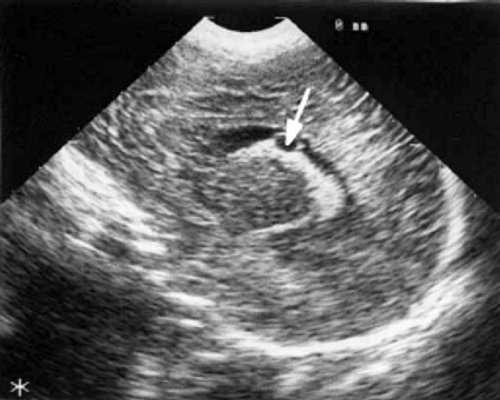

При эхоэнцефалографии у детей I группы выявлено от 1 до 3 изолированных кистозных структур (не сочетающихся с другими структурными изменениями) диаметром от 0,2-0,5 см (рис. 1, 2), расположенных в верхушке или теле сосудистого сплетения левого бокового желудочка. У 3-х из этих детей исходные данные вентрикулометрии соответствовали нормальным значениям. У 1-го ребенка отмечено незначительное (до 0,6 см) расширение межполушарной щели и субарахноидальных пространств по конвекситальной поверхности мозга и умеренное симметричное увеличение ширины лобных рогов (преимущественно) и высоты тел боковых желудочков (до 0,7 см).

Рис. 2. Эхоэнцефалограмма ребенка Д. с цитомегаловирусной инфекцией, 2-е сут. жизни. Стрелками обозначены кисты в теле сосудистого сплетения левого бокового желудочка.